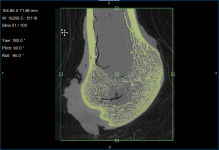

This section of the tutorial describes how to use the Bone Analysis module for 3D volume fraction plotting. You should note that volume fractions are scalar maps.

Comparison of volume fraction scalar map (on left) with vector-based field of anisotropy (on right)

- Create additional boxes to enclose different parts of the original region of interest, if required.

NOTE You can also use any of the boxes you created previously in this tutorial to map volume fraction.

- Choose the settings for the volume fraction map on the Mappings tab, as shown below.

- Click the Compute mapping button.

When processing is complete, the volume fraction dataset appears on the Data Properties and Settings panel.

- Examine the volume fraction map in the 3D or 2D views in the workspace.

NOTE In most cases, the Jet LUT provides good visualizations of volume fraction.